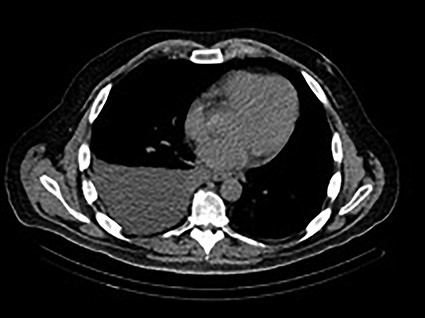

A 48-year-old male with a history of metastatic rectal cancer to the liver status post-folfox and bevacizumab, proctosigmoidectomy, coloanal anastomosis, hepatectomy and hepatic artery infusion pump placement (May 2019), who on December 2019 presented to thoracic surgery with a recurrent right pleural effusion (Fig. 1). Of note, the patient was asymptomatic from this effusion (Fig. 1). The patient’s last infusion using the HAIPC occurred on November 2019.

December 2019—CT chest: moderate to large right-sided pleural effusion.